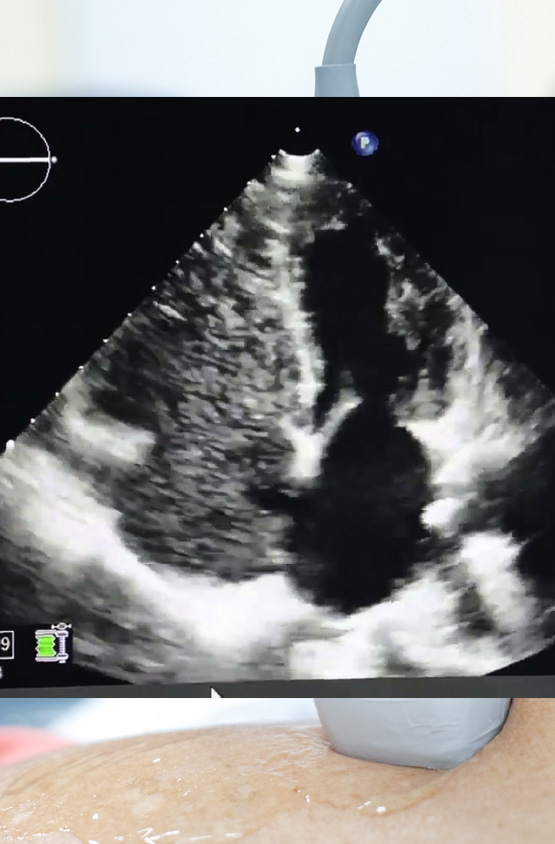

During the procedure: The technician uses the images from the echocardiogram to evaluate heart structures and function. The test may take about 30 to 60 minutes for routine and longer for specialized techniques. Specialized techniques include but are not limited to:In some cases, an ultrasound enhancer called Definity may be used to optimize the images. A bubble study may be ordered for certain indication like a stroke or TIA. Cardia strain analysis is often performed for oncology patients and for certain cardiac conditions such as Amyloidosis.

Visualize blood flow through the heart to detect any adnormal connections.